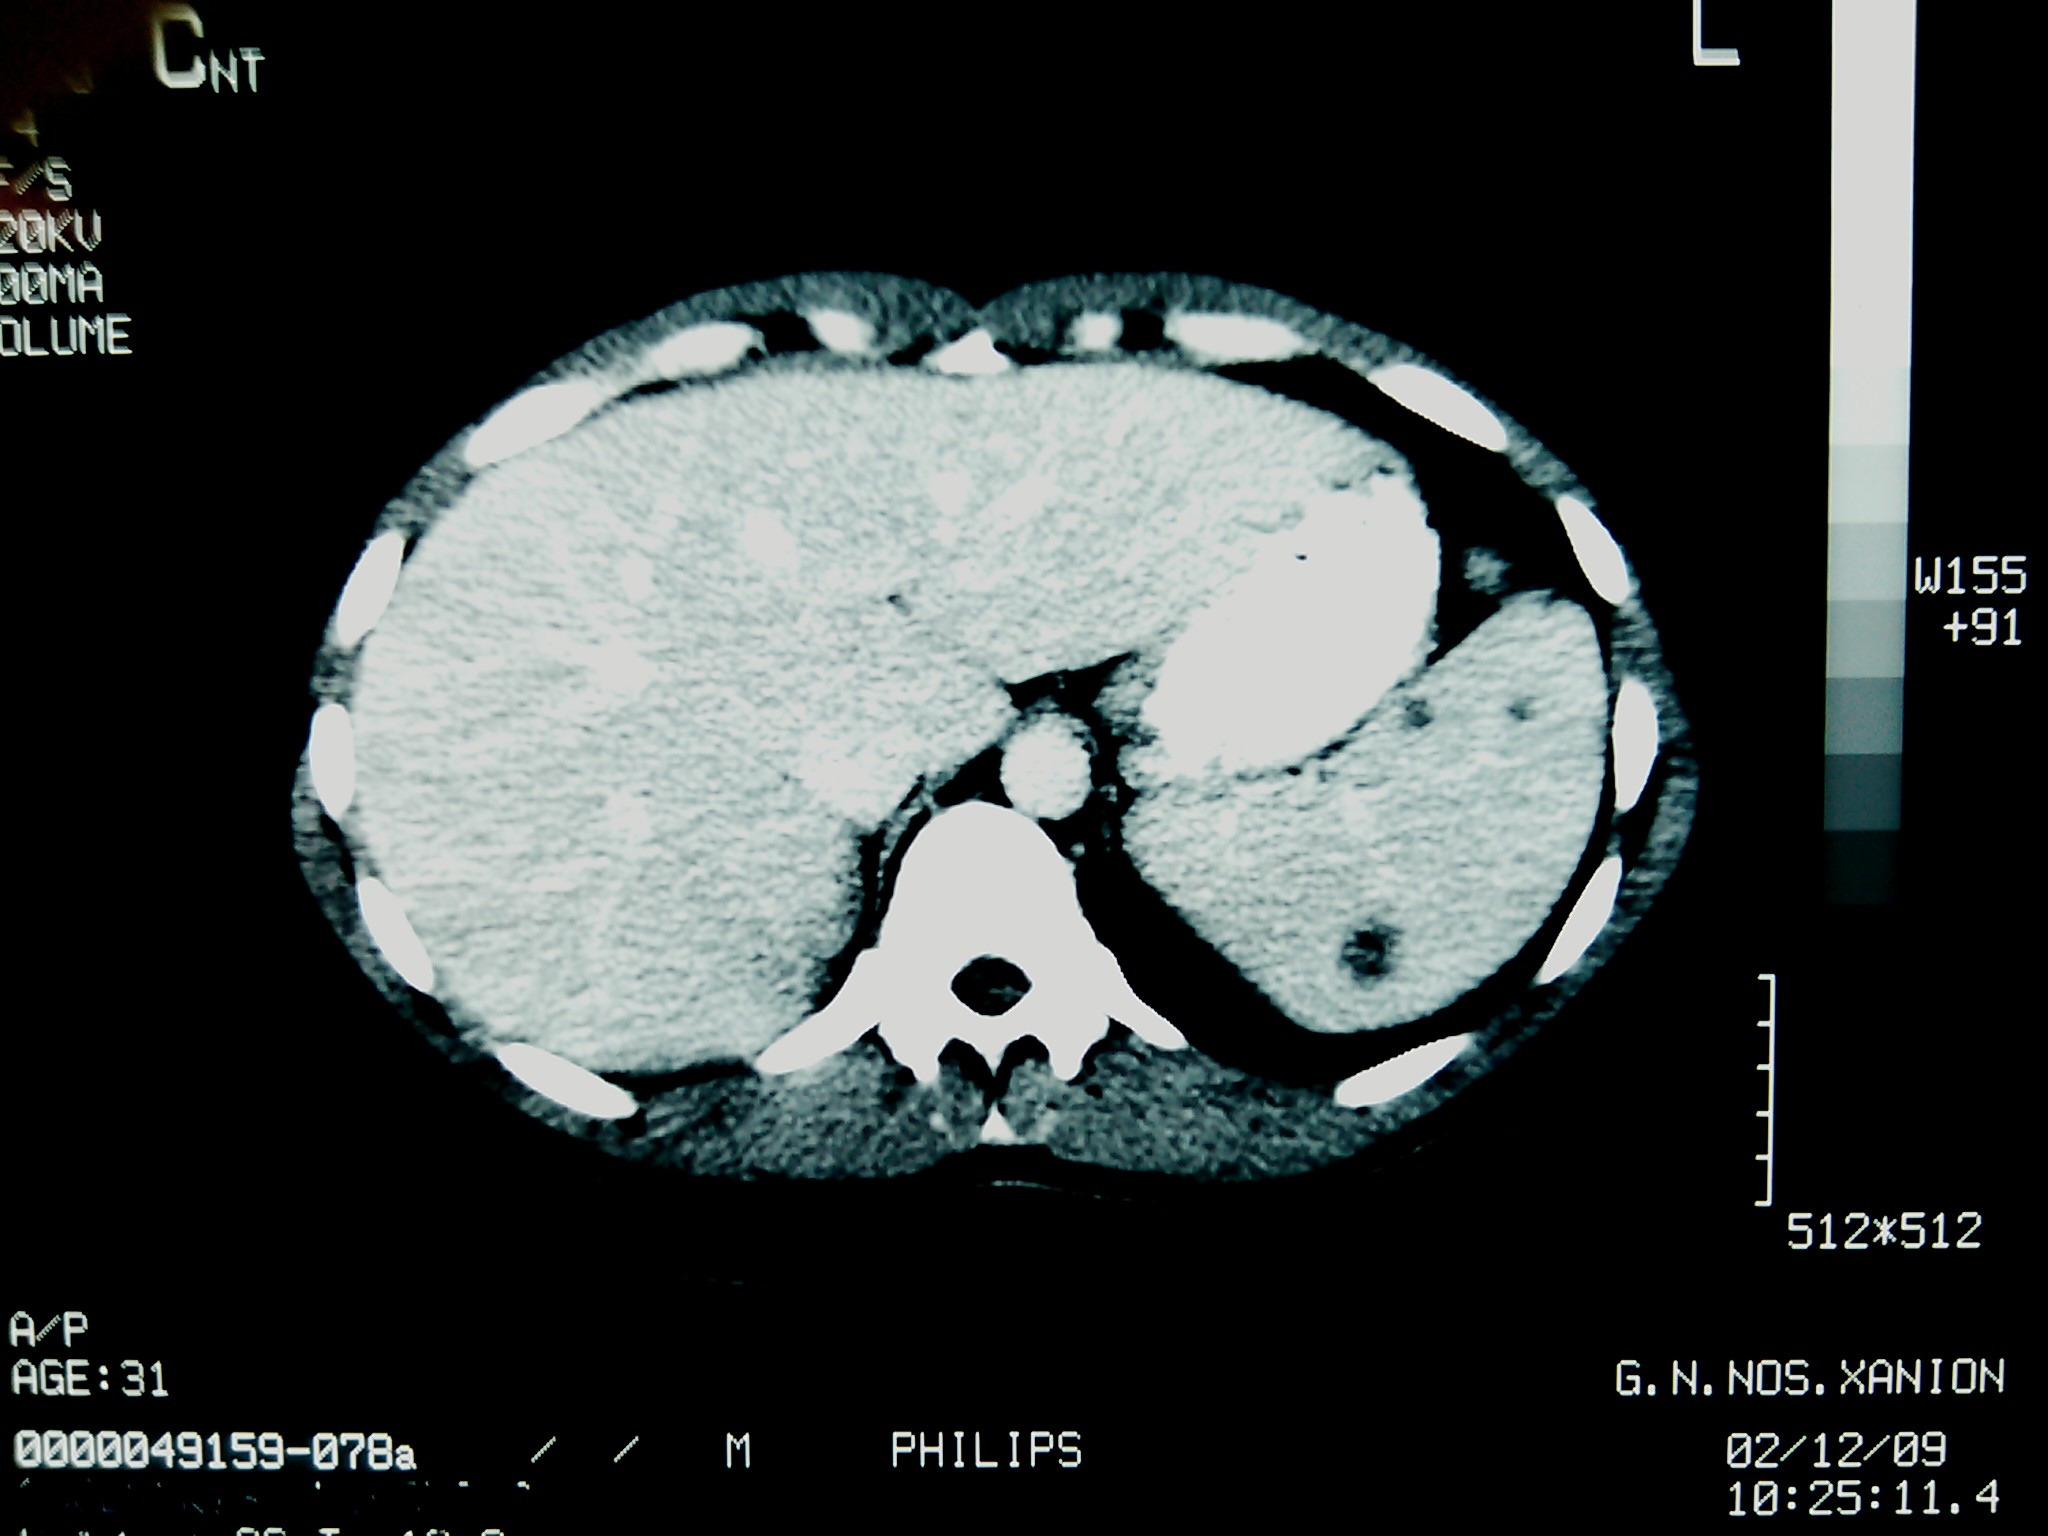

Adalimumab-Associated Isolated Splenic Tuberculosis In A Patient With Psoriasis Following A Negative Screening With Tuberculin Skin Test And QuantiFERON-Gold

We describe a rare form of extrapulmonary tuberculosis and, to our knowledge, the first reported case of isolated splenic tuberculosis in association with adalimumab treatment. In addition, our case demonstrates that the interpretation of a negative tuberculin skin test may prove problematic even in otherwise healthy individuals with no predisposing factors, especially in the face of biologic treatment. A history of BCG vaccination in adulthood may pose additional burdens in the evaluation of such patients facing the risks of anti-TNF agents. As to QuantiFERON, further investigation is warranted in order to be incorporated in the screening for latent tuberculosis infection.Downloads